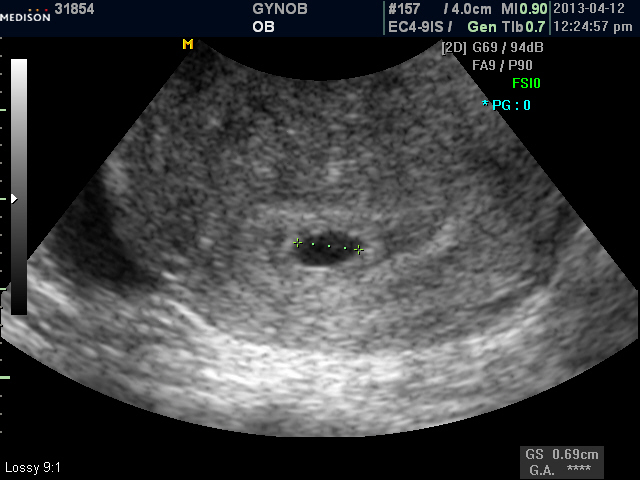

며칠 전에 초음파로 아기집을 확인하시고 "선생님, 되었어요.." 하고 저희 손을 잡아 주실 때 정말이지 눈물이 왈칵 쏟아지더군요..